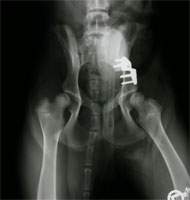

Es besteht keine Notwendigkeit von postoperativen Verbänden. Allerdings ist ein Belecken der Wunden ggf. durch Anlegen eines Halskragens zu verhindern. Unmittelbar postoperativ werden, solange sich der Patient noch in Anästhesie befindet, Kontroll-Röntgenaufnahmen angefertigt (Abb 12 und 13). Die deutliche Verbesserung der dorsalen Überdachung des Oberschenkelkopfes kann sofort gesehen werden. Die Lage des Implantates und der Schrauben werden kontrolliert.

DBO Röntgen präoperativ

Abbildung 12: Röntgen - präoperativ

DBO Röntgen postoperativ

Abbildung 13: Postoperative Röntgenkontrolle